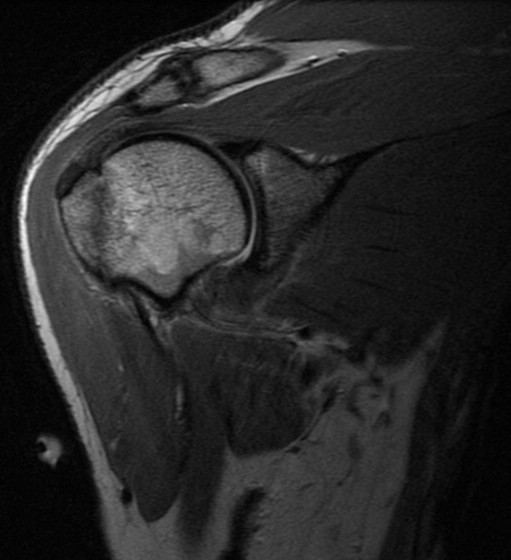

Injury. Possible dislocation

Subluxation or dislocation can result in a GT fx (essentially a hill sachs that progresses anteriorly). Rather than a bankart lesion, many times a capsular sprain will result without a labral detachment. The thickened edematous capsule will look like adhesive capsulitis but in this case has the traumatic history often not there with adhesive capsulitis.

Greater tuberosity fracture and capsular sprain